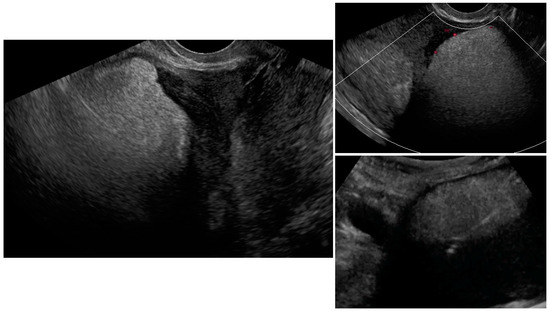

| Case Number (Age, Years Old) | Ultrasound Diagnosis of Uterine Lesion | Figure | Initial Treatment/ Histological Diagnosis Required (Doctor’s Decision) | Initial Patient’s Willingness to Undergo Surgery for the Uterine Lesion | Histology from Core Needle Biopsy | Patient Decision to Undergo Surgery for the Uterine Lesion | Histology from Definitive Surgery | Did Core Needle Biopsy Provided Additional Information to Ultrasound | Did Core Needle Biopsy Provided Useful Information for the Clinical Management |

|---|---|---|---|---|---|---|---|---|---|

| 7 (29) | Atypical uterine lesion | Figure A7 | Yes | Yes | Leiomyoma (UG-TUC core needle biopsy) | Yes | Leiomyoma with signs of degenerations | Yes | Yes |

| 8 (52) | Atypical uterine lesion | Figure A8 | Yes | Yes | Total abdominal hysterectomy performed without core need biopsy, because of patients age and lesion ultrasound pattern recognition. Note: frozen section result: leiomyoma | Yes | STUMP | - | - |